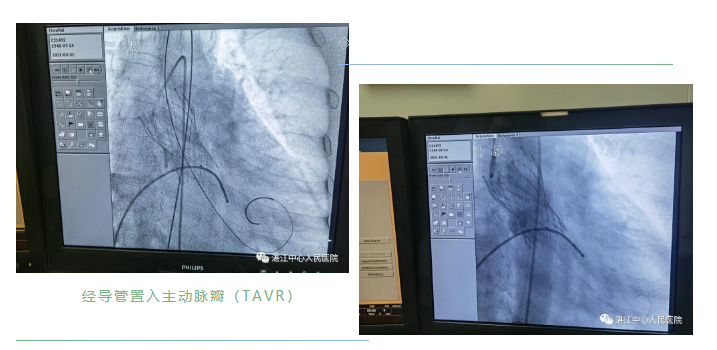

TAVR手术是通过微创介入的方式,从股动脉将人工心脏瓣膜输送至主动脉瓣区,释放后替代原来损坏的主动脉瓣,恢复瓣膜功能。与传统的开胸换瓣手术相比,具有创伤小,病死率低,术后并发症少,恢复快等优点,部分患者术后第二天就可以下地活动,该手术可以说是高龄患者的更好选择。

经过上述的充分准备,遂于3月31日上午在介入室,在孙华保、李泽林主任带领下,梁国钦副主任医师,冯明瑞、柯子奋主治医师上台在省医教授的指导下,先为患者植入右冠脉支架一枚,随后再顺利经导管置入主动脉瓣(TAVR),手术约两个小时,在介入室床边行心脏彩超提示跨瓣压差从术前的100mmHg到术后压差消失,术前EF47%到术后升到53%,效果显著,术后入ICU监护一天后转回心内一科普通病房,术后第一天即能下床活动,7天出院,岀院后一周回院复查,一切恢复良好,已无心衰及心绞痛的症状。